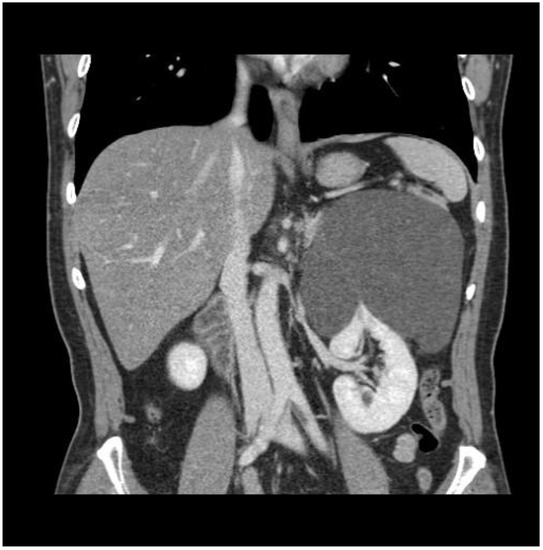

2. Case Report